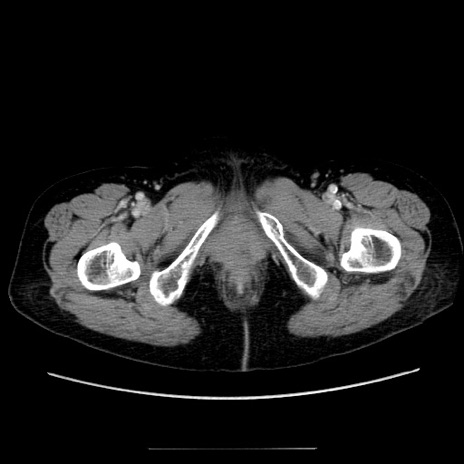

症例5(横断像)

【症例】70歳代女性

【主訴】お腹が張る

【現病歴】1週間くらい前から腹部膨満の自覚あり。昨日夜から増悪したため、本日救急外来受診。

【身体所見】意識清明、BT 36.5℃、BP 165/106mmHg、HR 80bpm、SpO2 98%、腹部:膨満、軟、自発痛・圧痛なし、触診にて不快感あり、腸蠕動音:減弱

【データ】WBC 12600、CRP 1.04